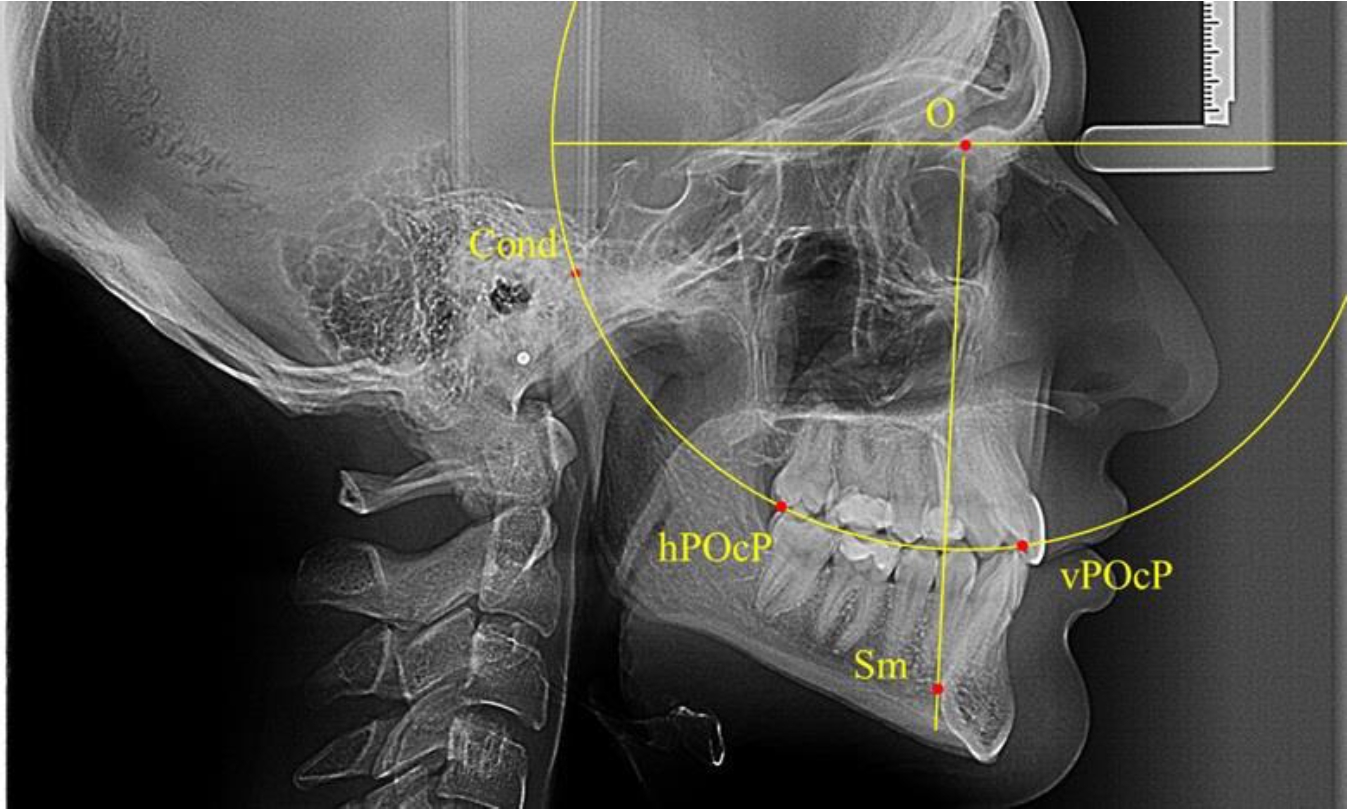

Результаты исследования рентгенограмм с мезотрузионным типом резцов показали, что линия Bimler проходила позади первых премоляров у людей с широким типом подбородочного выступа, однако окклюзия была физиологической и не требовала удаления премоляров, что носило рекомендательный характер при проведении подобных исследований при аномалиях прикуса. У людей со средними формами подбородочного выступа линия Bimler проходила впереди первых премоляров (рис. 2).

Аналогичная ситуация была у людей и с узкими вариантами подбородочного выступа.

Таким образом, при мезотрузионном типе зубочелюстных дуг расположение премоляра впереди линии Bimler при широких вариантах подбородка не может быть критерием выбора экстракционных методов лечения.

Рис. 2. Положение первых верхних премоляров при мезотрузии с широкими (а) и средними (б) размерами подбородка